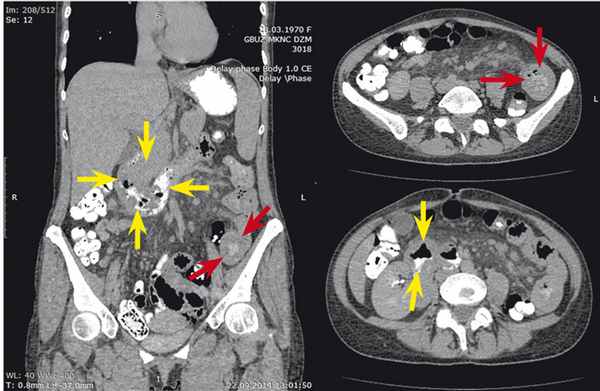

При проведении колоноскопии органической патологии со стороны толстой кишки выявлено не было. Больной была проведена мультиспиральная КТ органов грудной полости, брюшной полости и забрюшинного пространства ( рис. 4 ). В 7-м сегменте печени подкапсульно визуализирован очаг пониженной плотности 9 мм в диаметре, накапливавший контрастное вещество в позднюю и отсроченную фазу, подозрительный на очаг вторичной природы. При введении контрастного вещества per os определялись утолщенные до 22 мм за счет подслизистого слоя стенки двенадцатиперстной кишки в нисходящем и нижнегоризонтальном отделах, где контурировались множественные округлые и полигональные образования пониженной плотности размерами до 20 мм. Просвет двенадцатиперстной кишки сужен, деформирован. Аналогичные изменения отмечались в стенке тощей кишки (на расстоянии 60 мм от связки Трейца) протяженностью 125 мм. Ранее определявшиеся аналогичные изменения в стенке нисходящей и сигмовидной кишки не выражены. Лимфатические узлы брюшной полости и забрюшинного пространства увеличены: мезентериальные, парааортальные и паракавальные — множественные до 10 × 16 мм. Брыжейка тонкой кишки повышенной плотности, неоднородной структуры.

Рис. 4. Компьютерная томограмма органов брюшной полости больной В., 44 лет. Фото авторов.

Примечание. Желтыми стрелками отмечены патологические изменения двенадцатиперстной кишки, красными стрелками — патологические изменения тощей кишки